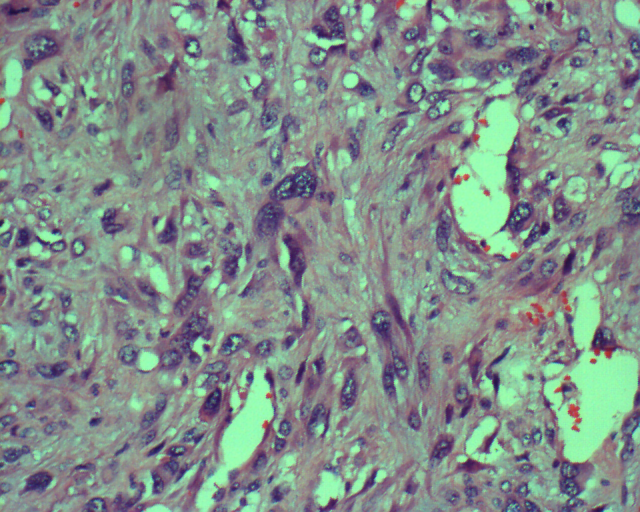

2.镜下

肿瘤由发生间变的组织细胞和纤维细胞构成,同时可见多核巨细胞和炎症细胞。伴有散在坏死出血灶。

图 3 组织学表现: 瘤细胞呈多形性改变,

有梭形、圆形、多边形,可见核明

显异型的多核巨细胞。